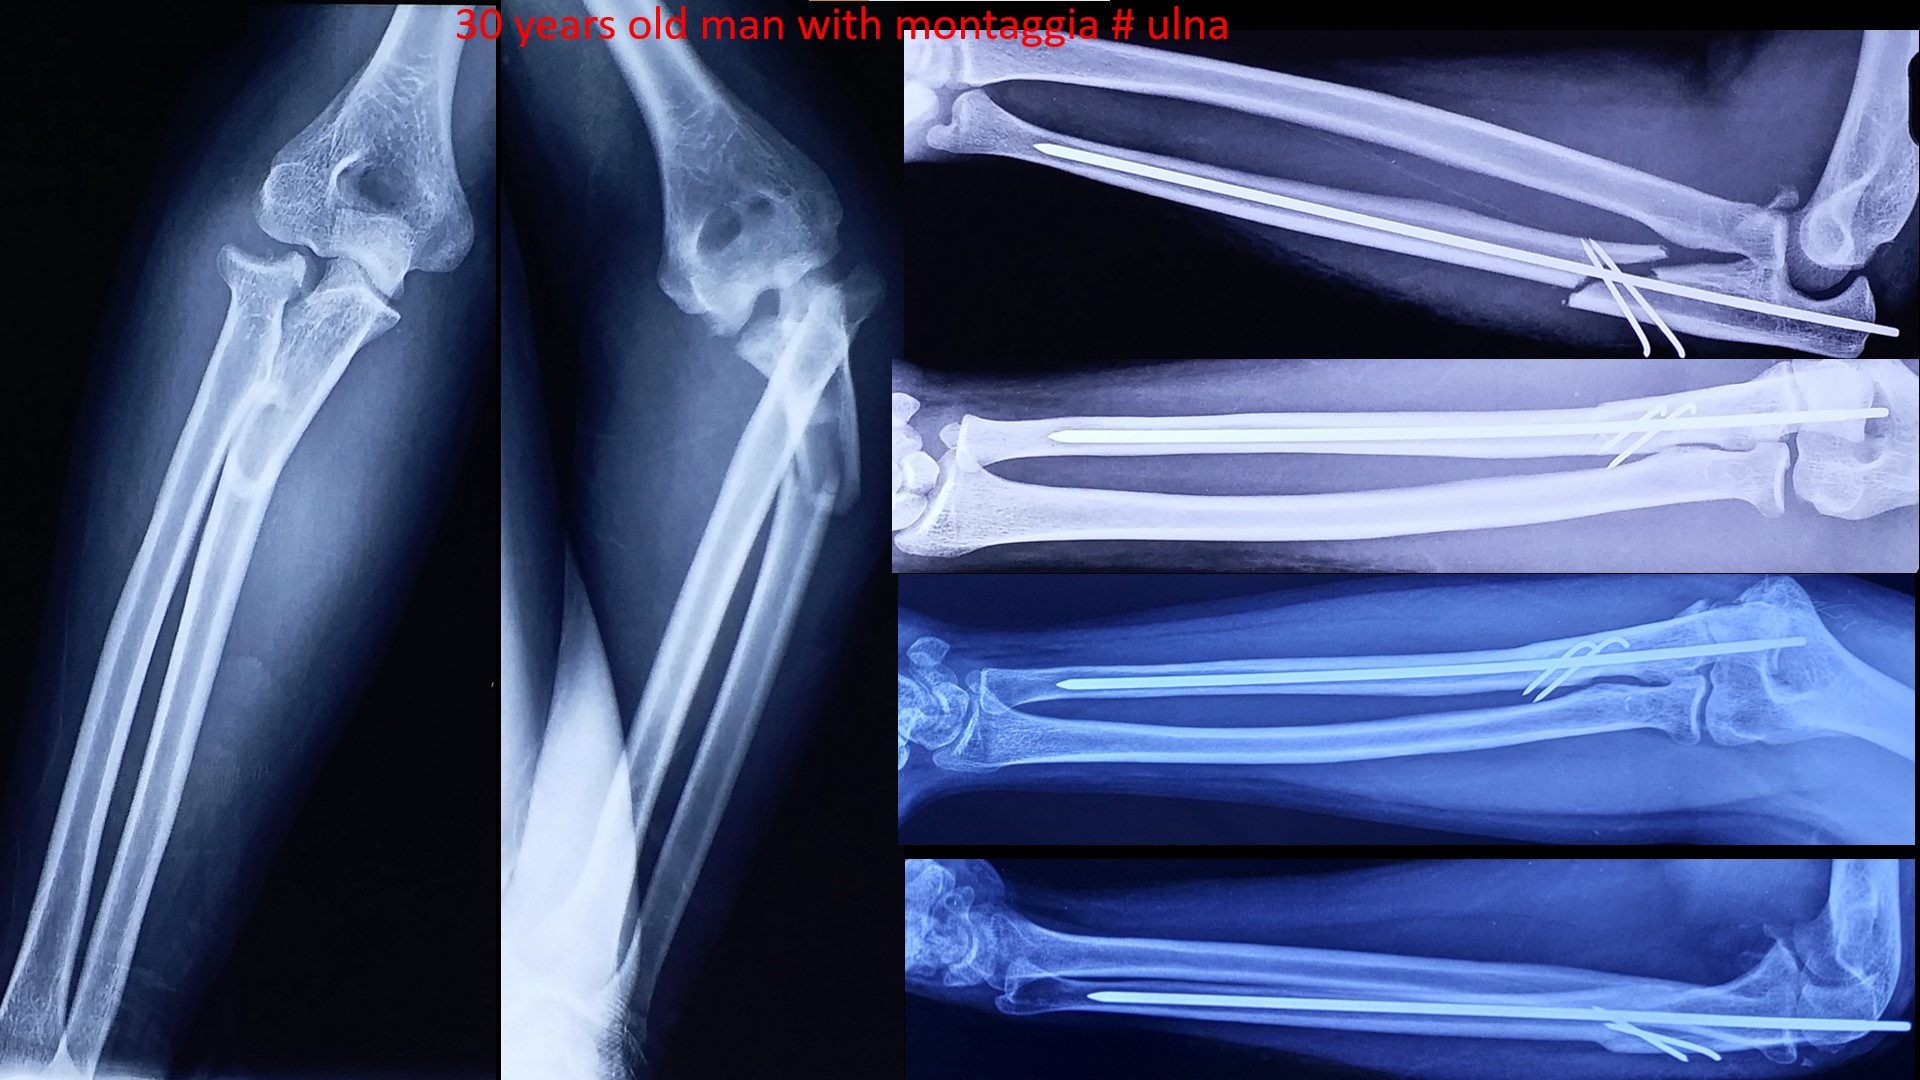

FOREARM FRACTURES